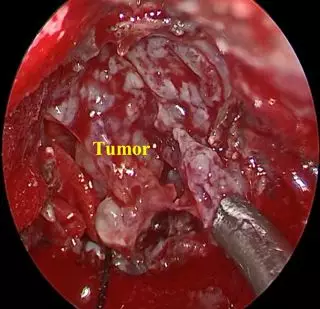

• Debulking Tumor

• After debulking, dissecting tumor margin

• Tumor in CPA, with 30° angle rigid